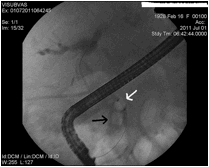

Η βασική ένδειξη της ERCP είναι η τοποθέτηση πλαστικής ή μεταλλικής ενδοπρόσθεσης (stent) για την αποσυμφόρηση του ίκτερου στις περιπτώσεις ανεγχείρητου καρκίνου της κεφαλής του παγκρέατος ή χολαγγειοκαρκινώματος, (δηλ καρκίνου του χοληδόχου πόρου, του κοινού ηπατικού πόρου, ή των πυλών του ήπατος). Η επιλογή του τύπου του stent εξατομικεύεται στον κάθε ασθενή. Σε γενικές γραμμές, τα πλαστικά stent αποφράσσονται από βακτηριδιακό υλικό ή ανάπτυξη του ίδιου του όγκου σε 3 μήνες κατά μέσο όρο, ενώ η βατότητα των μεταλλικών διαρκεί περισσότερο (περίπου 6 μήνες). Επίσης, υπάρχουν μεταλλικά stent μερικώς επικαλυμμένα για την αποφυγή της ανάπτυξης καρκινικού ιστού μέσα από τα κενά του πλέγματος τους (ingrowth). Επειδή τα μεταλλικά stent είναι πιο ακριβά, πρέπει να χρησιμοποιούνται μόνο στις περιπτώσεις που το προσδόκιμο επιβίωσης του ασθενούς είναι τουλάχιστον πάνω από 3-6 μήνες. Εικόνες  3 και 4.

Εικόνα 3. Ασθενής με εκτεταμένο χολαγγειοκαρκίνωμα Εικόνα 4. Τοποθέτηση πλαστικής

των πυλών του ήπατος (Klatskin tumor) και κλινική       ενδοπρόσθεσης (stent) στον προηγούμενο

εικόνα οξείας χολαγγειίτιδας.                                          ασθενή για την αποσυμφόρηση του ικτέρου και

της φλεγμονής πριν από τη χειρουργική

επέμβαση